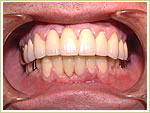

79歳 男性 インプラント埋入数:12本 画像拡大

治療前

治療中

治療後

治療中治療後